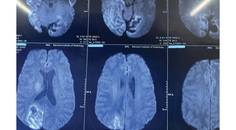

Disulfiram-Ethanol Reaction Causing Cortical Blindness

Noel James, MBBS, MD; Nirumal Khumar, MBBS, MDNoel James, MBBS, MD; Nirumal Khumar, MBBS, MD - Neuromuscular